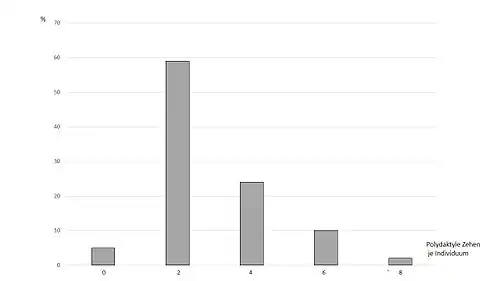

From an evo-devo point of view, polydactyly is a phenotypic variation or innovation, as the fingers and toes arise in places where nothing is phenotypically present in the wild type. Although it is initiated by a point mutation, it occurs as a polyphenism with different numbers of toes. The analysis of the additional toe numbers of Maine Coon cats revealed that the number of toes follows a developmental bias: 2 additional toes occur much more frequently than 4, these more frequently than 6 or 8 additional ones.[34] Also, for the evo-devo theory, polydactyly cannot be adequately explained by genetic mutation alone, but only by constructive development, i.e. the ability of development to produce a complex phenotypic output. The corresponding symbolic generation of toes can now be shown in computer models.[35]